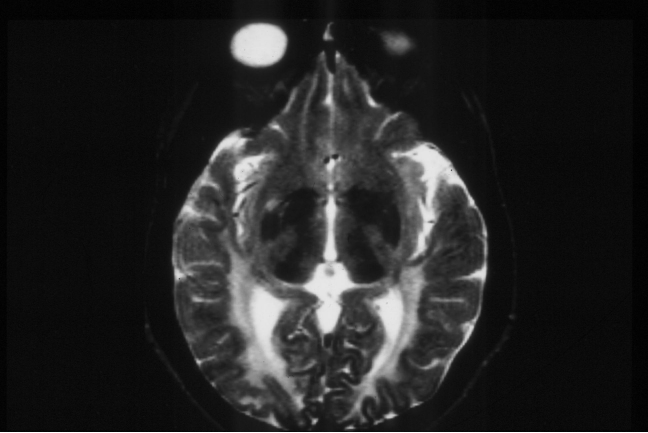

PKU MRI - abnormal white matter

Even in treated PKU there are neurological consequences-

learning, executive function problems etc